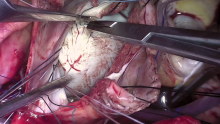

Dr. Vince Gaudiani found the sinus venous defect when he was ready to place a right superior vein vent and discovered that the right superior pulmonary vein (RSPV) was draining into the superior vena cava (SVC). The right atrium was then opened, and the small-bore catheter (SBC) cannula was moved into the innominate vein. Prior to repairing the sinus venosus defect, the mitral valve was approached through the defect.

An initial repair was attempted, but eventually it required replacement. The sinus venosus defect was addressed with a baffle and the tricuspid was repaired with a 34 mm annuloplasty ring.